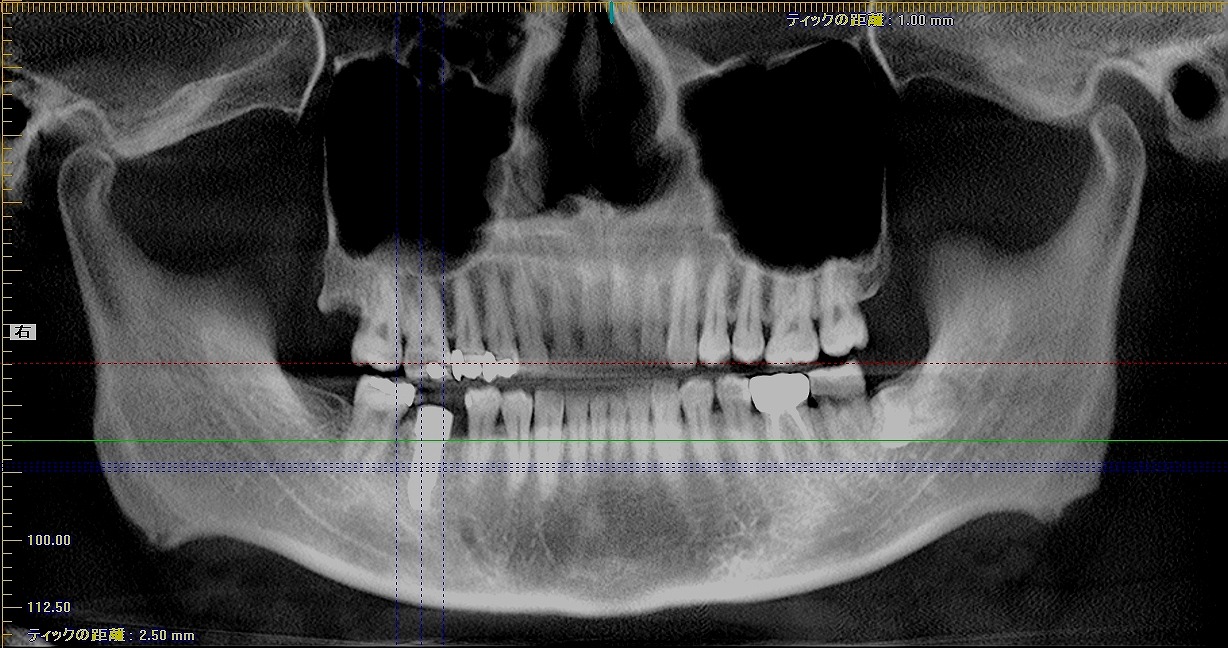

右下の6番部の抜歯即時インプラント埋入 インプラント治療の臨床現場 40代男性|お知らせ |広島市安佐南区の歯科医院 右下の6番部の抜歯即時インプラント埋入 インプラント治療の臨床現場 40代男性 トップ お知らせ・ブログ お知らせ 右下の6番部の抜歯即時インプラント埋入 インプラント治療の臨床現場 40代男性 右下の6番部の抜歯即時インプラント埋入 インプラント治療の臨床現場 40代男性 ずっとほったらかしにしていた歯になります 保存不能な状態 抜歯を行っていきました インプラント窩を形成 インプラント埋入を行っていきます 骨補填材を転入していきました 縫合して終了となります 術前のCTになります 術前術後のCTになります 術前術後のパノラマになります Web診療予約 初めての方へ 選ばれ続ける理由 院内設備について 歯が痛いしみる一般歯科 歯がぐらぐらする歯周病 健康な歯を保ちたい予防歯科 子供の虫歯予防をしたい小児歯科 銀歯をセラミックに審美歯科 白い歯を目指しませんか?ホワイトニング 矯正専門医がいるので安心矯正歯科 抜けた歯を補いたいインプラント・入れ歯 医院案内 スタッフ紹介 メリィハウス歯科クリニックオフィシャルホームページ ラベンダー歯科クリニックオフィシャルホームページ お知らせ・ブログ ホーム 診療科目 一般歯科 歯周病治療 予防治療 小児歯科 審美治療 ホワイトニング 矯正歯科 入れ歯・インプラント マウスピース矯正 初めての方へ 院長・スタッフ 設備紹介 医院案内・アクセス メニューを閉じる